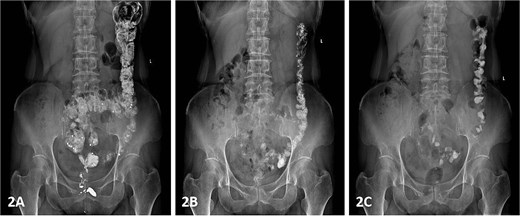

Postoperatively, the patient was administered intravenous cefuroxime and metronidazole for 3 days as prophylactic antimicrobial therapy. The iodine-impregnated vaginal gauze pack and indwelling urinary catheter were removed 24 h after surgery. Daily vaginal dressing changes were performed, involving thorough wound disinfection with povidone-iodine. In cases of excessive vaginal discharge, additional irrigation with normal saline was conducted. The interrupted silk sutures on the posterior vaginal wall were removed during a follow-up visit 2 weeks postoperatively. At 15 days postoperatively, following suture removal, repeat defecography demonstrated a residual RC depth of 11 mm, with complete resolution of the patient’s defecatory dysfunction (Fig. 5). During the 24-month postoperative follow-up period, the patient maintained normal defecatory function with no recurrence of obstructive symptoms. However, repeat defecography was not performed due to the patient’s personal preference.

Postoperative defecography at 15 days, the image demonstrates a residual RC depth of 11 mm.